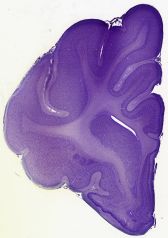

Datasets -> Felis Catus -> CV, (Cresyl Violet), coronal, histo, Single-hemisphere, adult

[ Metadata ]   ·   Source: R. Glenn Northcutt Collection, MCZ-Harvard   ·   [ R. Glenn Northcutt Collection info ]

Displaying Sections 1 thru 40 of 86 Sections for this Dataset